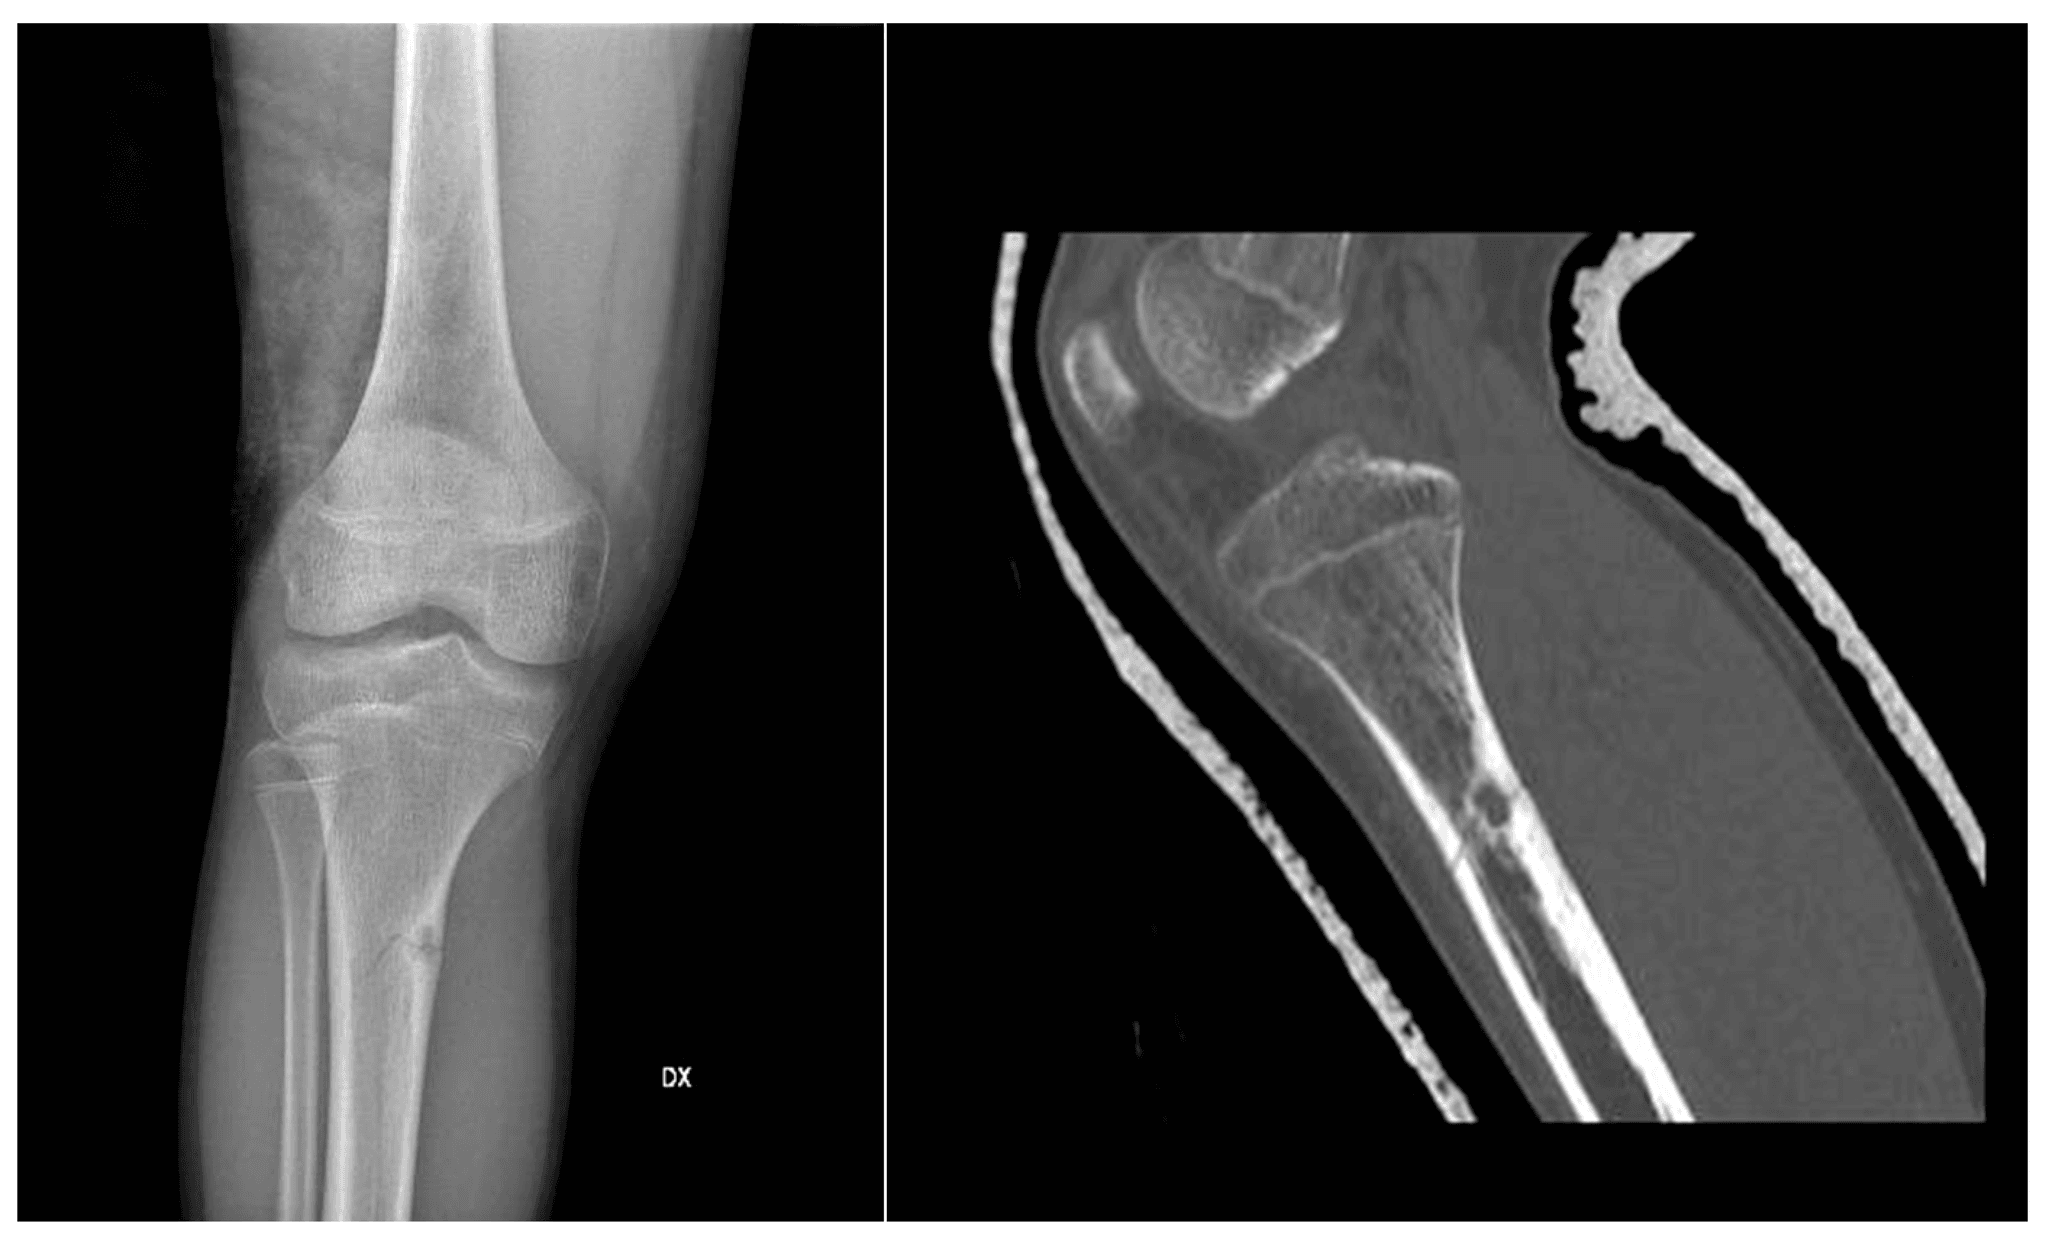

For the right treatment, an accurate diagnosis is essential. Evaluation usually consists of: